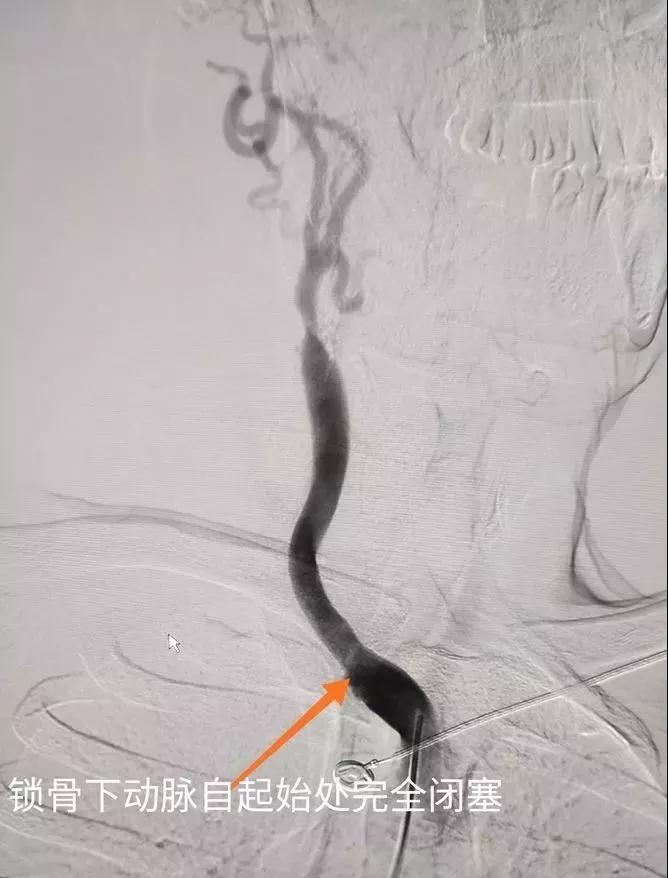

患者行腦血管造影后,發(fā)現(xiàn)右鎖骨下動脈慢性完全閉塞,右頸內(nèi)動脈完全閉塞,右頸外動脈及左椎動脈代償右椎動脈血流,右頸內(nèi)動脈血流緊靠左椎動脈部分代償供血。如不及時開通右鎖骨下動脈,患者腦供血無法改善,有造成偏癱及昏迷風(fēng)險!

與患者家屬充分溝通后,我們決定給患者開展鎖骨下動脈再通手術(shù)。常規(guī)右側(cè)股動脈穿刺入路開通,但是由于右鎖骨下動脈開口處完全閉塞!怎么辦?有人提出放棄治療?